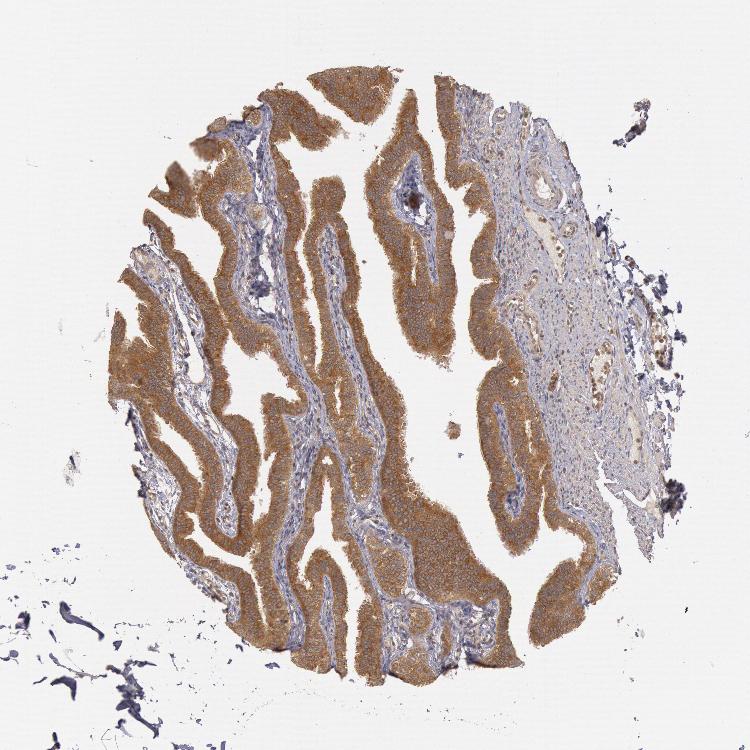

SEMINAL VESICLE - Antibody stainingi

Antibody staining in the annotated cell types in the current human tissue is reported as not detected, low, medium, or high, based on conventional immunohistochemistry profiling in selected tissues. This score is based on the combination of the staining intensity and fraction of stained cells.

Each image is clickable and will lead to virtual microscopy that enables deeper exploration of all samples and also displays staining intensity scores, fraction scores and subcellular localization as well as patient and tissue information for each sample.

Antibody HPA001328Antibody HPA071048Antibody CAB004552Antibody CAB080447Antibody CAB080451Antibody CAB080531

Glandular cells HighMediumMediumLowLowHigh